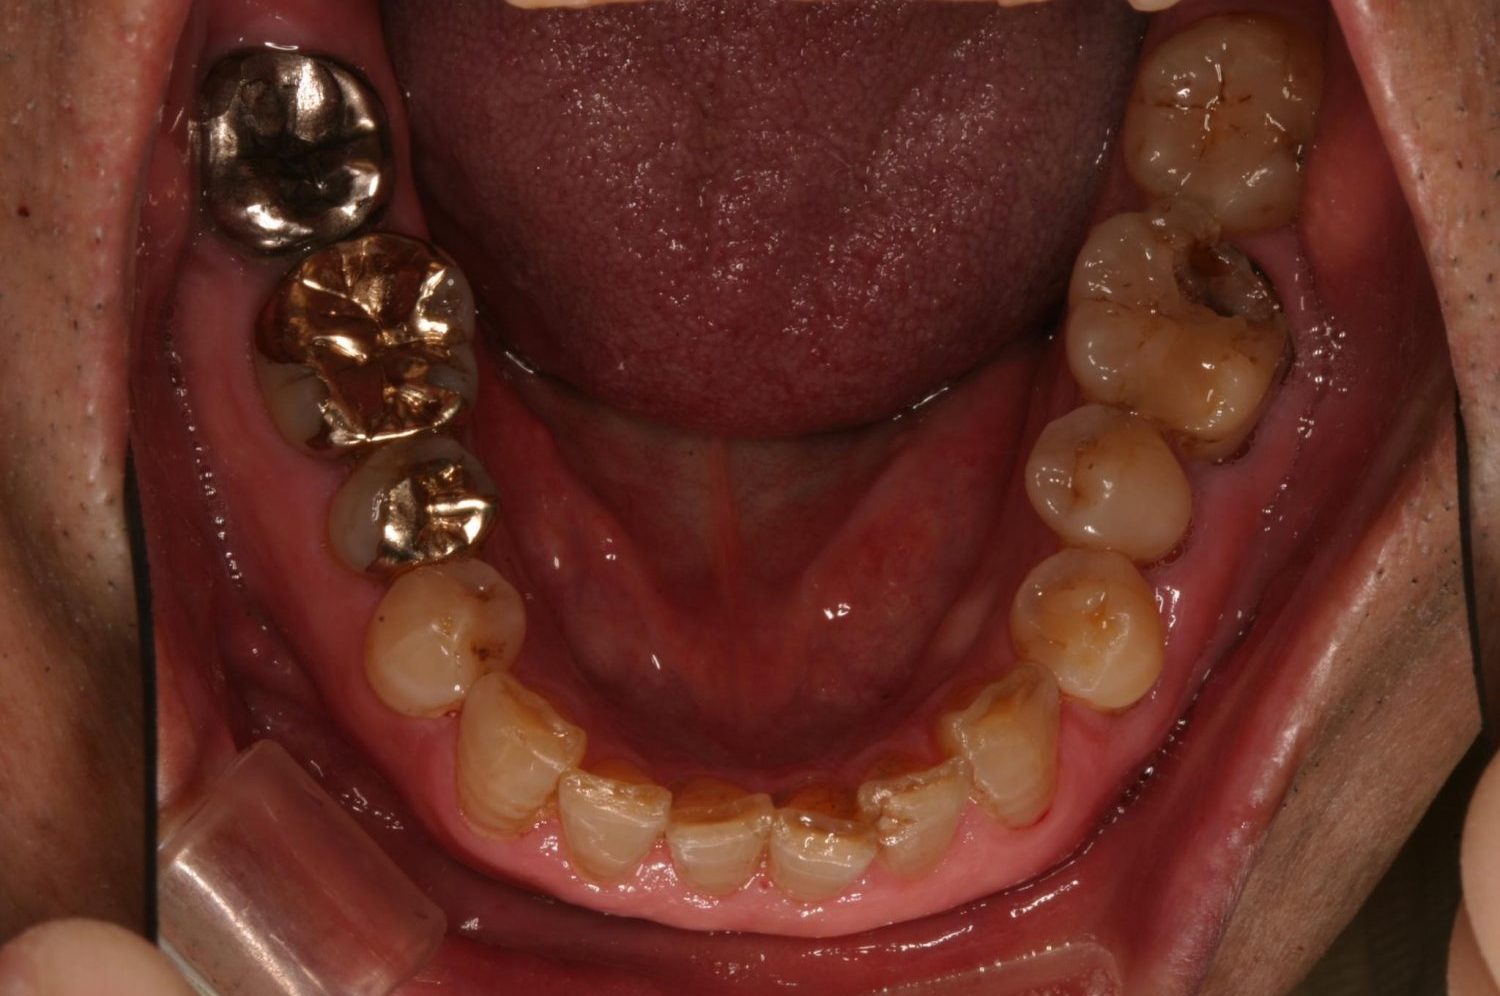

インプラント治療の症例紹介③

Before

After

主訴

むし歯の治療

治療内容

保存不可能な歯の抜歯

下顎にインプラント埋入し咬合再構成

治療費

2,688,400円(税込)

治療期間

14か月

治療回数

21回

想定されたリスク

※上部構造の形態が複雑になるため清掃が難しくなる。インプラント周囲炎の恐れがありました。

多数歯う蝕および多数歯欠損による咬合崩壊、保存不可能な歯の抜歯により上下無歯顎に。下顎に6本インプラント埋入する事で咬合再構成を行った。